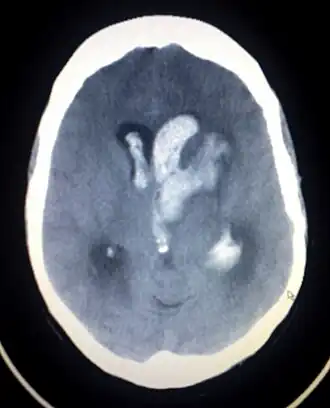

Компьютерная томограмма спонтанного внутримозгового кровоизлияния с прорывом крови в желудочки головного мозга

Компьютерная томография — метод выбора в диагностике внутричерепных кровоизлияний.